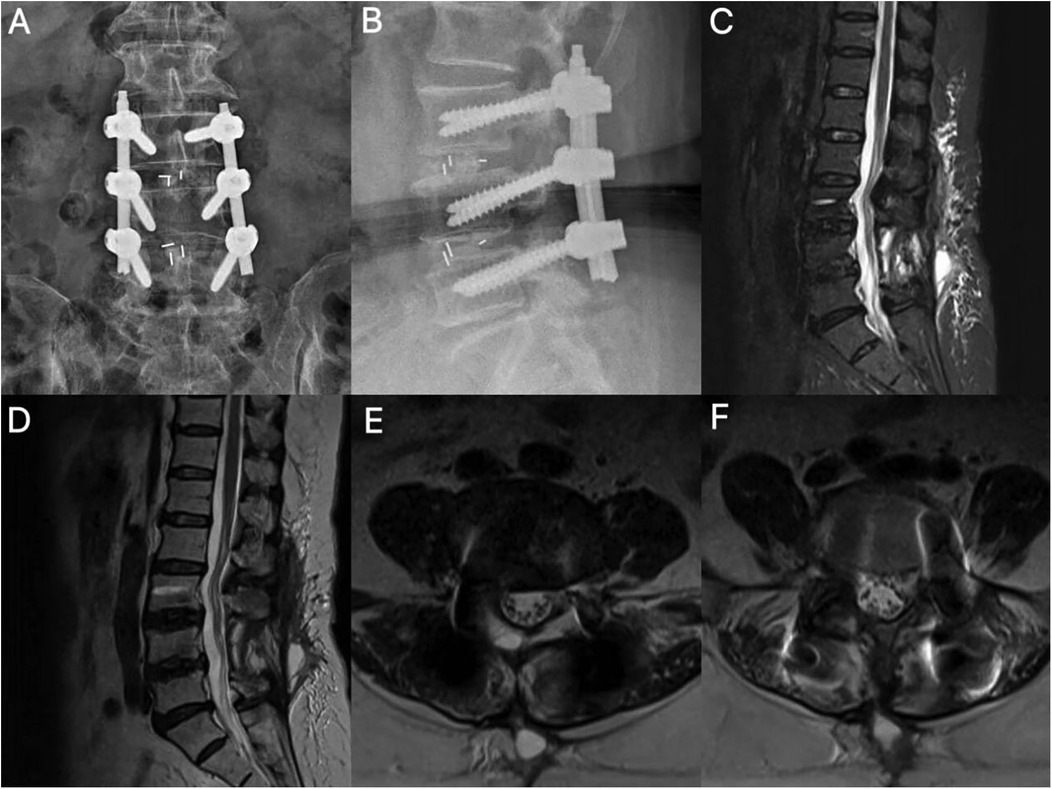

On postoperative day 2, the patient reported significant relief of bilateral lower limb pain, with the VAS score improving to 3 points, representing a marked improvement compared to preoperative levels. By day 5, the VAS score worsened to 7 points, and new-onset bilateral lower limb numbness (particularly around the knees) accompanied by shooting pain emerged. These symptoms showed no significant improvement after treatment with corticosteroids and neurotropic agents. On day 7, numbness progressed with the development of saddle anesthesia, and bilateral lower limb muscle strength decreased to grade IV (Table 1). Repeat imaging demonstrated satisfactory reduction of spondylolisthesis with appropriate cage positioning and screw placement on lumbar radiographs. Lumbar MRI revealed no spinal stenosis or nerve root compression, showing instead expanded spinal canal volume without space-occupying lesions or foraminal obstruction. However, axial MRI sequences displayed positive nerve sedimentation signs, and the cauda equina exhibited a hyperintense, high-tension state (Figure 2).

Figure 2. Postoperative imaging. (A,B) Lumbar radiographs demonstrate accurate positioning of L3–L5 pedicle screws and optimal interbody cage placement. (C,D) Sagittal MRI reveals spinal canal expansion and localized epidural fibrosis. (E,F) Segments L3–4 and L4–5 are shown with no space-occupying lesions; note the ventral cauda equina apposed to the dural sac in a hypertension state with a positive sedimentation sign (+).

Traditionally, postoperative neurological complications following spinal surgery have been attributed to direct mechanical compression (e.g., hematoma, fusion device displacement) or ischemic injury. However, the pathological core of ILNBD lies in the pathological increase in neural axial tension, which can independently cause disease even in the absence of obvious space-occupying compression (6, 7). In this case, the patient's symptoms improved early postoperatively, suggesting that the initial decompression was effective (8). However, on the fifth day, the patient suddenly developed progressive worsening of sensory-motor deficits in both lower limbs and numbness in the saddle region. Imaging studies ruled out common causes such as hematoma, shunt displacement, or residual compression, but axial MRI showed a positive nerve descent sign (9, 10). This finding strongly suggests that the cauda equina has lost its normal floating relaxation state and is in an axial traction state, consistent with the characteristic imaging findings of bowstring disease.

Upon reviewing the surgical procedure and relevant literature, we believe that the occurrence of iatrogenic lumbosacral neural arch string disease in this case was most likely due to technical errors in the highly controlled intervertebral fusion technique. Although the spinal cord and nerve roots possess a certain degree of elasticity, the surgeon relied on experience to select the size of the fusion device, neglecting the stepwise testing of the intervertebral spreader, which led to excessive expansion of the intervertebral space. This maneuver directly caused sustained static traction on the nerve roots and cauda equina at the nerve root exit point, resulting in progressively increasing axial tension and ultimately leading to neural conduction blockage (11–13). From a neurobiomechanical perspective, the pathological process is not merely simple mechanical traction. Although the spinal cord and nerve roots possess some elasticity, neural tissue has a critical threshold for tolerating traction injury. When axial tension applied to the cauda equina and nerve roots exceeds their physiological range of extension, this persistent static traction first compresses the microvascular system within the nerves, obstructing blood flow. This leads to ischemia and hypoxia of the nerve fascicle sheath, causing ischemic damage to the nerves. These injuries ultimately result in neurological dysfunction, triggering symptoms such as pain and sensory abnormalities (12, 14). The diagnosis of ILNBD is often insidious because it lacks specific clinical manifestations and is easily confused with common postoperative conditions such as nerve root compression, epidural fibrosis, or even early inflammatory reactions (3). Symptoms often appear several days or even later after surgery and progressively worsen. Conventional dehydration and hormone therapy often yield poor results, further complicating diagnosis. Imaging is key to differential diagnosis. The diagnostic turning point in this case was the axial MRI: although sagittal and coronal views showed enlarged spinal canal volume, no mass lesions, and unobstructed nerve root exit, the axial plane clearly captured the characteristic “positive sedimentation sign” (15, 16). The sedimentation sign (Lack of Nerve Root Sedimentation Sign) refers to the failure of the cauda equina nerve bundle to settle to the dorsal side of the dural sac under the influence of gravity in the supine axial MRI, instead tightly adhering to the ventral sac wall, strongly suggesting that the nerves are in a state of axial high tension and have lost their normal floating relaxation (17). This sign is of significant value in identifying nerve traction injuries without obvious compression. Therefore, for patients who develop unexplained, progressive neurological dysfunction postoperatively, it is essential to carefully analyze axial MRI sequences to identify features of cauda equina syndrome, such as high tension and the sedimentation sign, to avoid misdiagnosis or missed diagnosis (18).